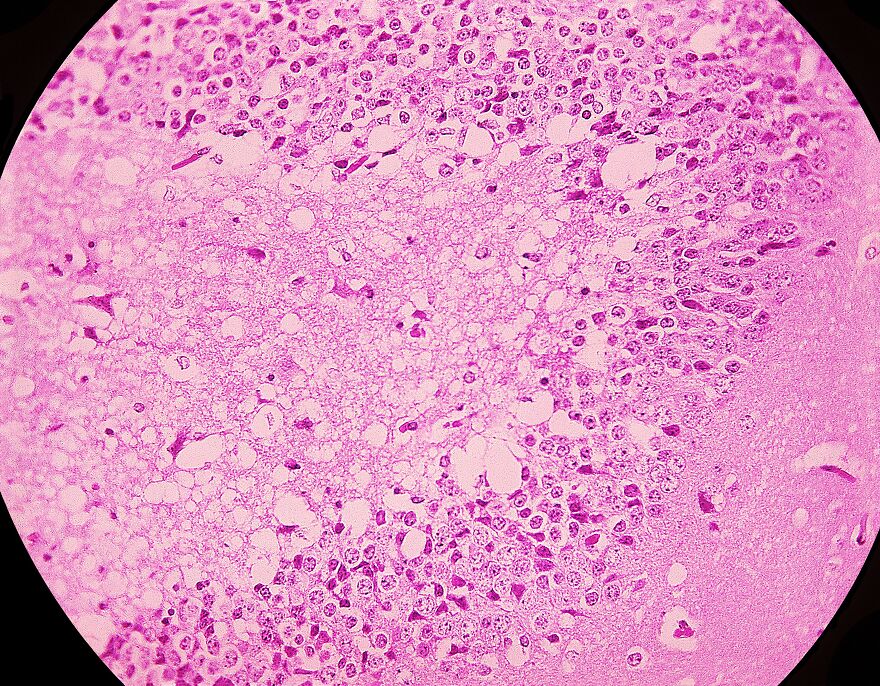

Trypophobia on Skin

The term “trypophobia skin” refers to the discomfort or disgust people experience when viewing clusters of holes or bumps on human skin. This reaction may be partly due to certain medical conditions that create similar patterns.

Most images shared online under this label are not real medical photos. They are typically digital edits or makeup effects made to exaggerate hole-like textures. Some use lotus pods or other natural textures blended with skin images to provoke a response.

The Dermatology Online Journal explains that while strong feelings of disgust or fear can occur, these reactions are based on perception and disease-avoidance instincts. They are not caused by actual illness.

Since trypophobia is not a recognized skin disorder, the term is often used in online hoaxes and fictional images. These may unfairly stigmatize harmless skin conditions. If you notice any unusual or persistent skin changes, it is important to focus on real symptoms rather than visual discomfort.